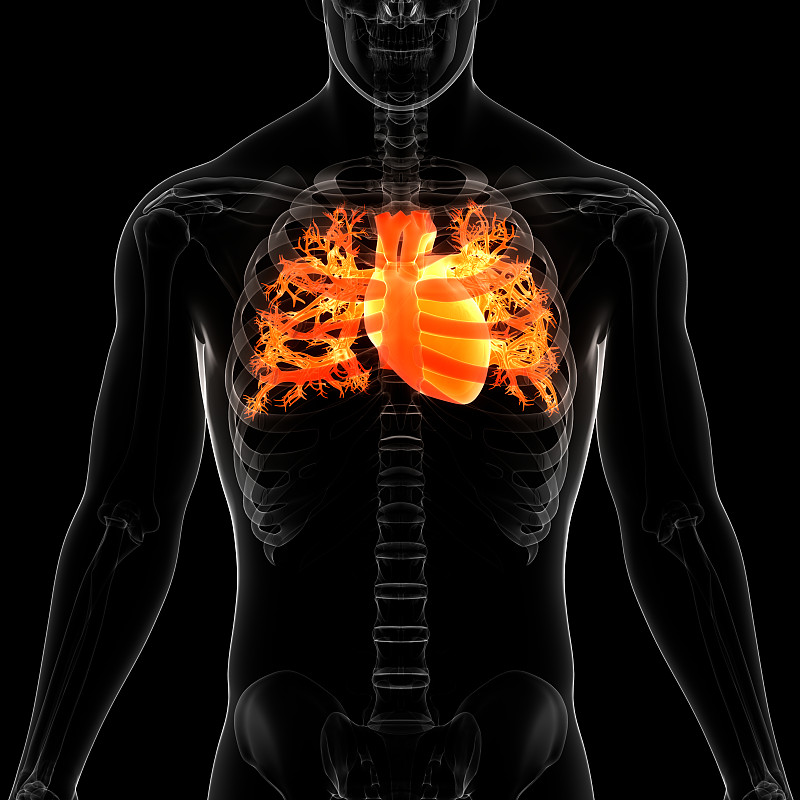

人体循环系统心脏解剖详情

JPG

人体循环系统心脏解剖详情

JPG

人体循环系统心脏解剖详情

JPG

人体循环系统心脏解剖详情

JPG

人体循环系统心脏解剖详情

JPG

人体循环系统心脏解剖详情

JPG

人体循环系统心脏解剖详情

JPG

人体循环系统心脏解剖详情

JPG

人体循环系统心脏解剖详情

JPG

人体循环系统心脏解剖详情

JPG

人体循环系统心脏解剖详情

JPG

人体循环系统心脏解剖详情

JPG

人体循环系统心脏解剖详情

JPG

人体循环系统心脏解剖详情

JPG

人体循环系统心脏解剖详情

JPG

人体循环系统心脏解剖详情

JPG

人体循环系统心脏解剖详情

JPG

人体循环系统心脏解剖详情

JPG

人体循环系统心脏解剖详情

JPG

人体循环系统心脏解剖详情

JPG